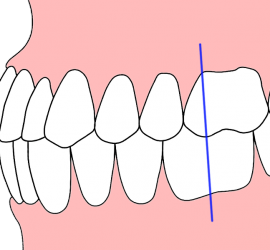

Аппарат представляет собой проволочный нёбный бюгель, который используется для стабилизации положения моляров, после лечения дистализирующими аппаратами, а так же для предотвращения потери места при лечении с удалением зубов. Жёсткая фиксация кнопки Нансе с кольцами создает прочную конструкцию для удержания достигнутого результата лечения.